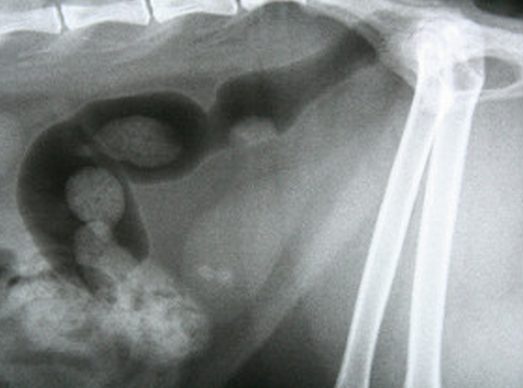

Bonjour ! Avez-vous parlé de la blessure à votre vétérinaire ? Avez-vous pris rendez-vous avec votre animal ou vous a-t-il conseillé par téléphone ? Une radiographie est nécessaire pour exclure une lésion de la moelle épinière au niveau lombosacré (cette partie de la moelle épinière est responsable de la défécation et de la miction), car une blessure dans cette région peut provoquer une incontinence.